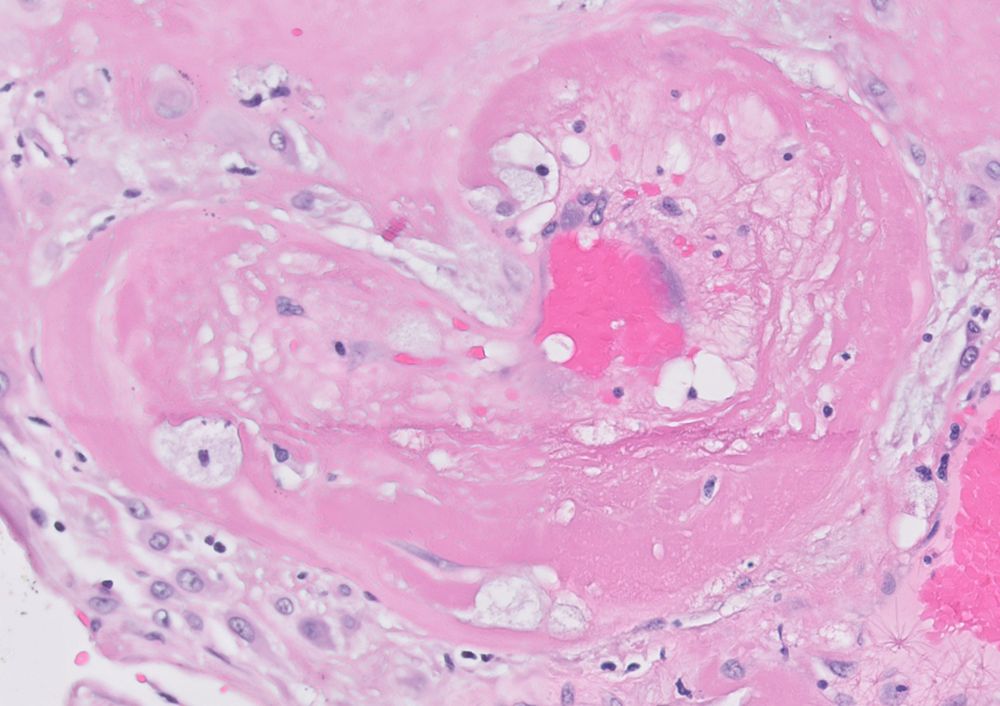

Gynecologic Pathology